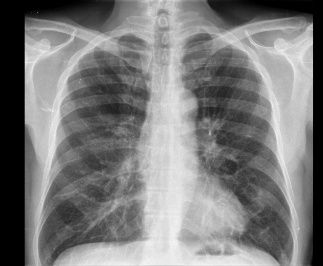

Image

Ground Truth

Base Model

Fine-tuned Model

Cardiomegaly with aortic elongation and perihilar interstitial pattern.

Cardiac silhouette is enlarged. Pulmonary vascularity is within normal limits. There is minimal linear atelectasis in the right mid lung. No focal areas of consolidation are present. There is no pleural effusion or pneumothorax. Degenerative changes are present within the spine.

Cardiomegaly. Aortic elongation. Pulmonary parenchyma without major alterations.